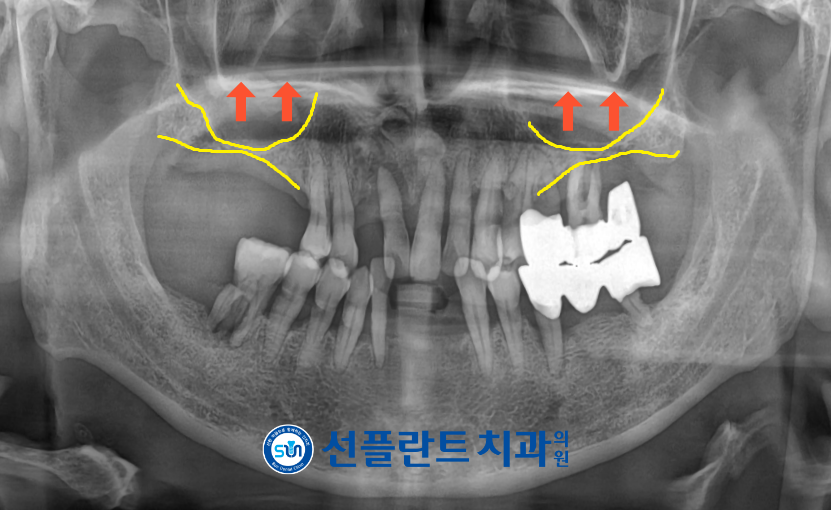

정밀한 검사를 위해

파노라마 사진을 촬영해 보았더니

만성 치주염으로 인해

전반적인 치조골 소실이 확인되었습니다.

김량장동치과 용인선플란트치과에서는

치아의 상태를 면밀하게 검사하여

빨간색 화살표 표시의 치아는

그대로 살려

치경부위에 닳아진 부분에

레진으로 메워 줌으로써

더 이상 치아가 마모되는 것을

막아주기로 하였으며,

노란색 동그라미 표시의 치아들은

신경치료 후 크라운 수복을 통해

치아를 보존하는 치료를

도와드리기로 하였습니다.

그 외의 나머지 잔존 치아들은

골소실과 동요도가 심한 상태로

예후가 좋지 않다고 판단하여

발치 후 임플란트 식립을

도와드리기로 치료 계획을 수립하였는데요.

위턱 양측 어금니의 경우

상악동 막이 아래로 내려와 있고

잔존 치조골 부족으로 인해

임플란트를 식립하기에는

수직적인 거리가 부족하여

일반 임플란트 식립이 어려운 상태였습니다.